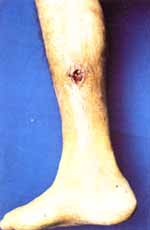

En el aspecto lateral de la pierna derecha se observó una úlcera de 2×3 cm de diámetro mayor, de la cual exudaba una sustancia gruesa y blanquecina (Figuras 3 y 3A).

Figura 3. Ulcera de 2×3 centímetros localizada en el aspecto lateral de la pierna derecha que muestra exudación de cristales de urato monosódico a través de ella.

Figura 3A. Acercamiento de la lesión descrita en la figura 3.